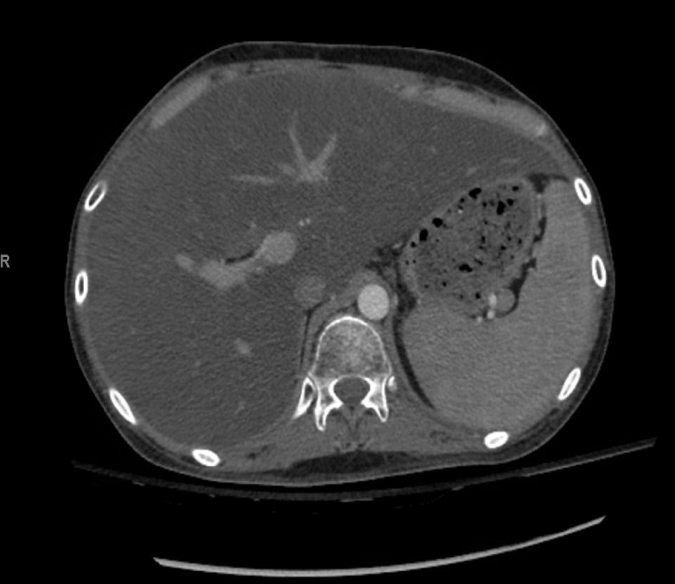

On the first admission, he presented with fever, lower extremity edema, and a generalized rash sparing the palms and soles. He had pancytopenia, elevated ferritin, and elevated liver enzymes, and a computed tomography (CT) scan of the abdomen showed small ascites and hepatosplenomegaly (Figure 1). Liver biopsy results showed fatty liver.

Figure 1. Abdominal CT scan showed hepatosplenomegaly and ascites.